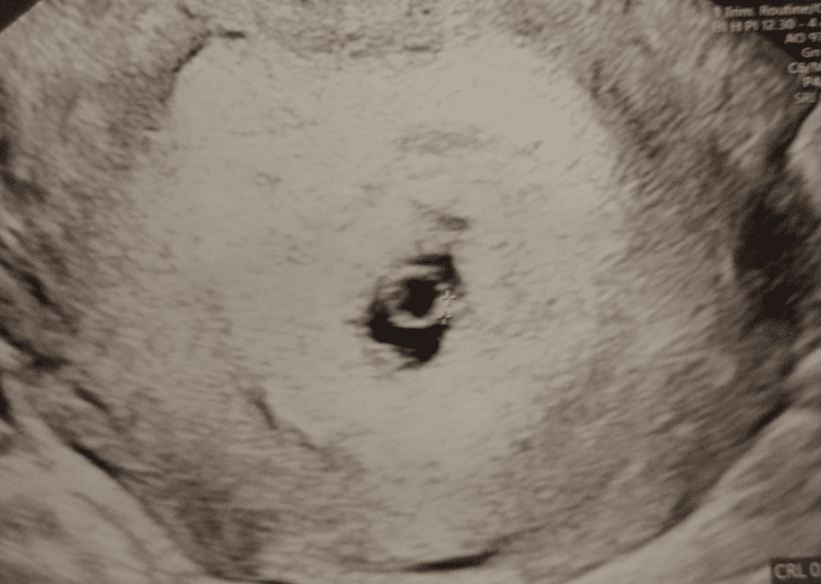

pokażesz fotkę usg? Może masz z okresu 6-7 tc?

U mnie był taki w 5/6 tygodniu. W 7 tygodniu byłam i okazało się wszystko w porządku, serce biło. Jutro mam kolejna wizytę, ale ciągle się boję, bo objawów brak..

Załączniki

• IMG_20230821_125007796.jpg

IMG_20230821_125007796.jpg

1,4 MB · Wyświetleń: 89